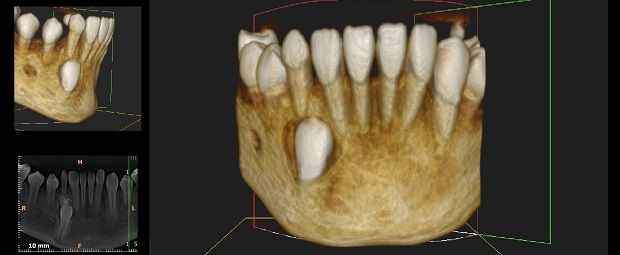

Contar con la más moderna tecnología permite una óptima visualización de piezas dentarias y estructuras óseas, articulares y musculares.

A las técnicas tradicionales como la radiología, sumamos estudios de avanzada para asistir a las prácticas de alta complejidad médica incluyendo la Tomografía Computada Cone Beam el más moderno sistema de imágenes odontológicas y maxilofaciales.